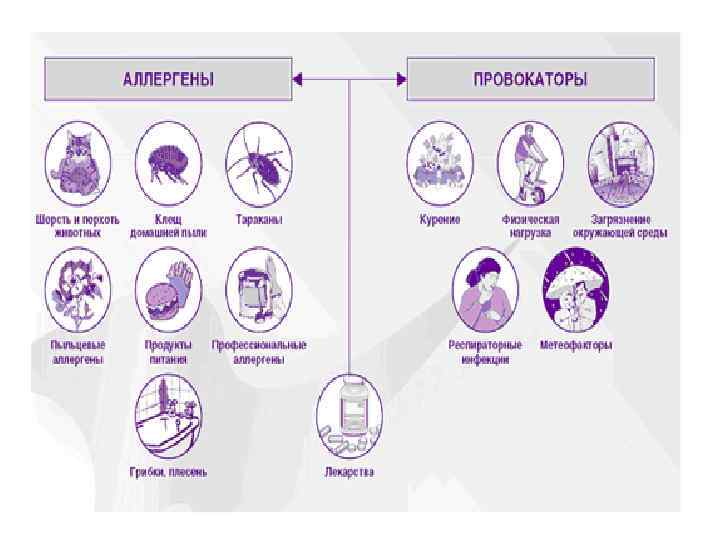

Факторы риска бронхиальной астмы Предрасполагающие: • Наследственность • Атопия Причинные факторы: Аллергены : • Бытовые • Пищевые • Пыльцевые • Лекарственные • Профессиональные Триггеры: • Курение • Респираторная инфекция • Загрязнение среды • Физические нагрузки • Аллергены • Климатические факторы • Стрессы